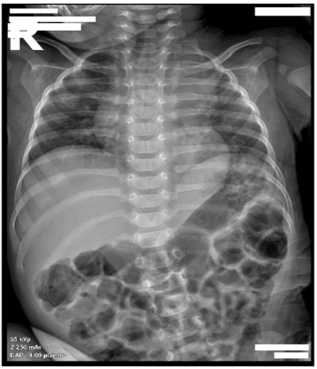

Abdominal Pain, a Rare Manifestation Revealing Takayasu's Disease: A Case Report

N Hazzab, B Khouadri, K Khabbach, Y El Boussaadni and A Oulmaati. 13(12): 01-04.